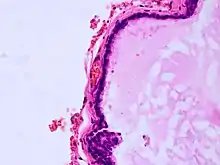

| Histopathology of colloid cyst |

A colloid cyst is a non-malignant tumor in the brain. It consists of a gelatinous material contained within a membrane of epithelial tissue. It is almost always found just posterior to the foramen of Monro in the anterior aspect of the third ventricle, originating from the roof of the ventricle. Because of its location, it can cause obstructive hydrocephalus and increased intracranial pressure. Colloid cysts represent 0.5–1.0% of intracranial tumors.[1]